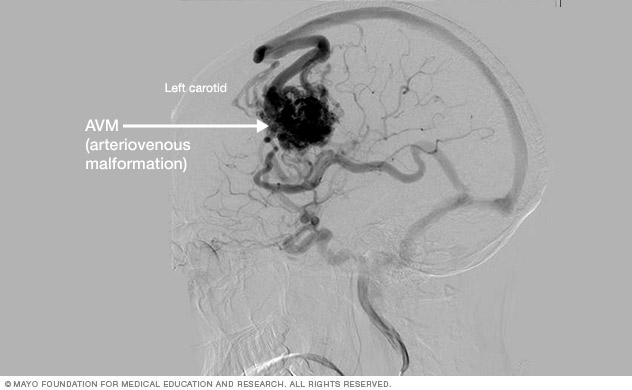

Brain AVM Angiogram

Cerebral angiogram showing brain AVM

• Cerebral angiography. Also known as cerebral arteriography, this is the most detailed test to diagnose a brain AVM. Cerebral angiography reveals the location and characteristics of the feeding arteries and draining veins, which is critical to planning treatment.

In this test, a long, thin tube (catheter) is inserted into an artery in the groin or wrist and is threaded to the brain using X-ray imaging. A dye is injected into the blood vessels of the brain to make them visible under X-ray imaging.